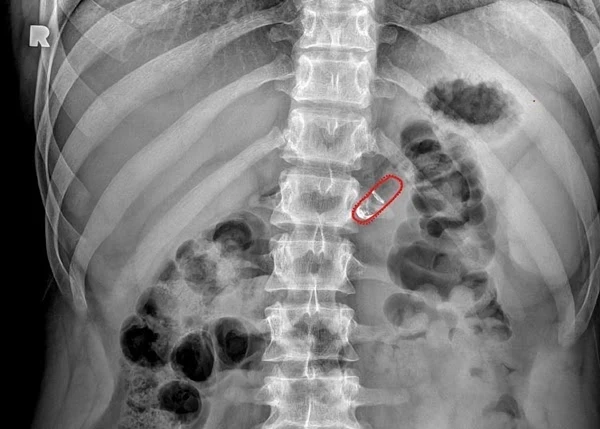

그림과 같이 약을 삼키면 소화기관을 따라 이동하다가 소장 내 특정 pH 환경에서 알약의 껍데기가 용해 됩니다. 그러면 내부 반응제들이 섞여 이산화탄소를 만들고, 압력차로 만드는 작은 풍선을 부풀려 약물이 든 바늘이 소장 벽에 꽂혀 주사될 수 있도록 설계 되었습니다. 이 때 이 바늘에는 체내에서 흡수가 가능한 약 성분이 포함되어 있고 주사가 끝나면 소장 내 나머지 알약 구조물은 체외 밖으로 배출되는 방식인데요. 이 알약 로봇에는 금속이나 스프링이 포함되어 있지 않아 몸에 염증을 일으킬 가능성이 적고, 금속 대신 주사가 가능한 등급의 중합체로 만들어졌다고 합니다.